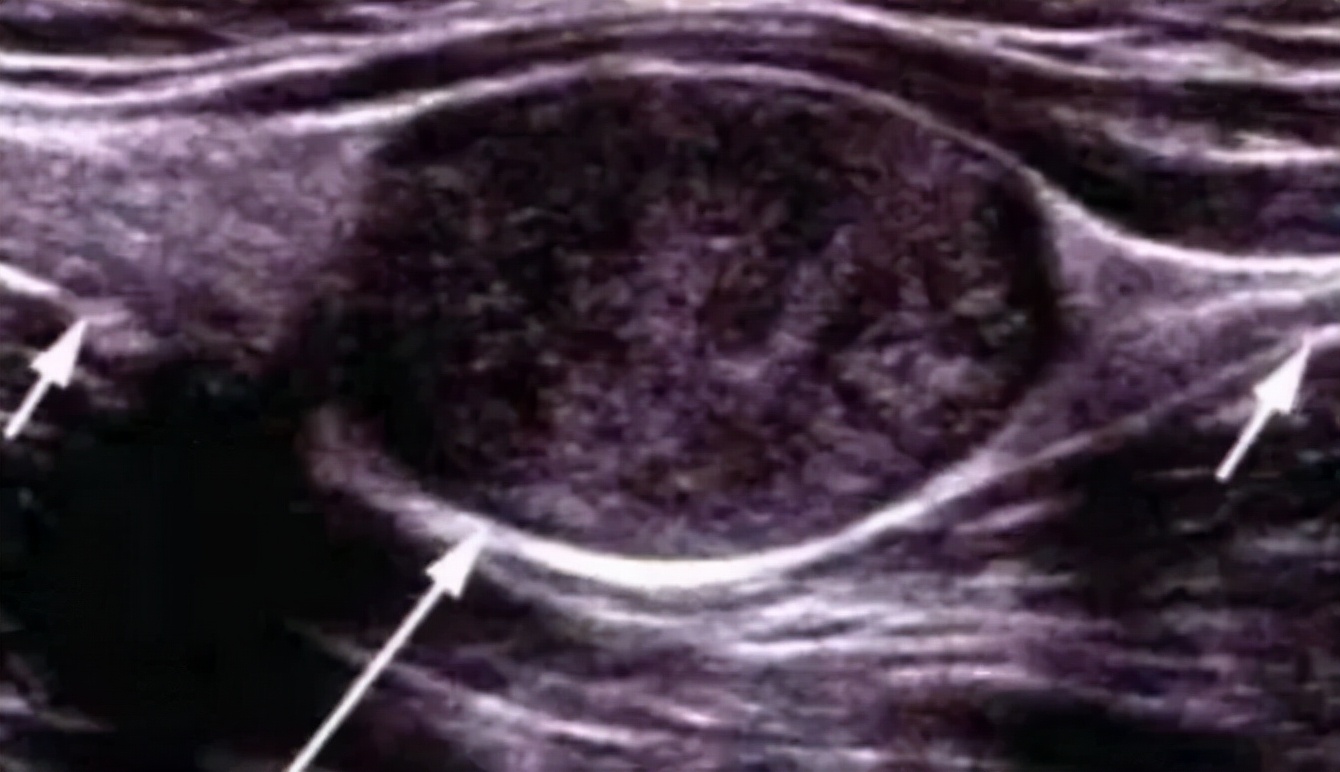

肌骨彩超提示:右侧颈7横突与颈肋相连,右侧臂丛神经下干受压。

就是彩超诊断这个大爷多了根肋骨,这根多的肋骨压迫到神经,导致了手麻。然后大爷再去拍了x片和磁共振,进一步证实了超声的诊断。

红线描绘出肿胀受压的臂丛下干